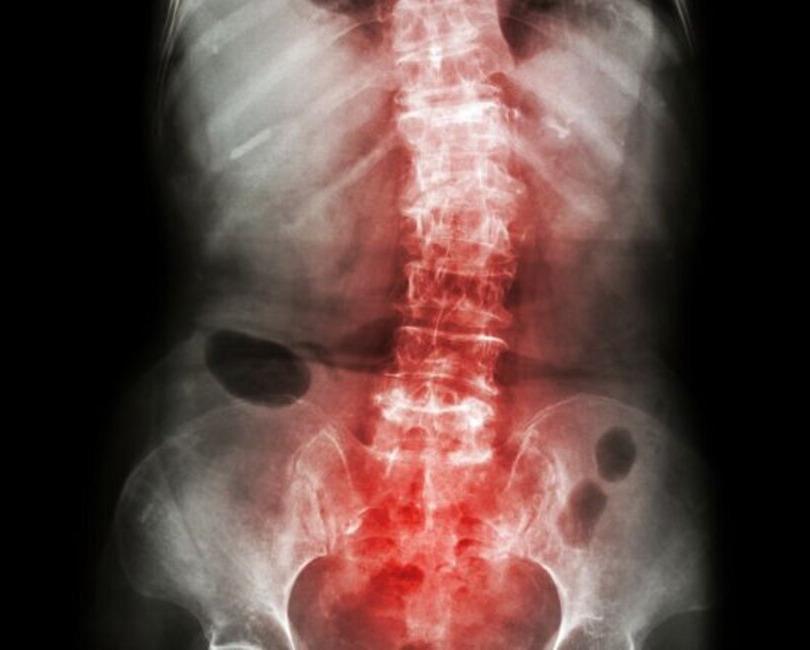

The treatment typically starts with a thorough diagnosis, including physical examinations and imaging tests like X-rays or MRIs, to determine the severity of the condition. Once diagnosed, a multidisciplinary approach is often adopted. This may include physiotherapy to improve flexibility and strength, medications such as anti-inflammatory drugs to manage pain, and in severe cases, surgical interventions like spinal fusion.

This stage involves identifying the type and extent of spondylitis through clinical evaluation, imaging tests (X-rays, MRI), and blood tests. Accurate diagnosis is essential for crafting a targeted treatment plan.